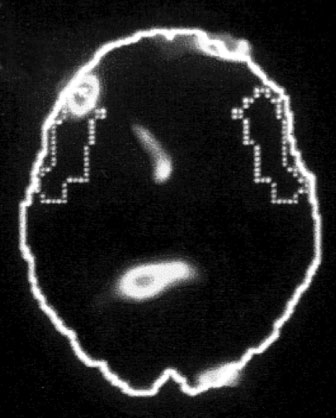

Сдвиг в одну сторону мозга

Снимки также показали, что во время этих живых болезненных воспоминаний у наших подопытных активировалась лишь правая часть мозга. В настоящий момент имеется множество научной и популярной литературы на тему различий между правым и левым полушарием. В начале девяностых мне доводилось слышать, что кто-то начал делить мир на людей с развитым левым (преобладает рациональное мышление, логика) и правым (интуиция, творческие способности) полушариями, однако тогда я не придал этой идее особого значения. Тем не менее наши снимки явно демонстрировали, что образы о пережитой травме активируют правое полушарие мозга, отключая при этом левое.

Теперь нам известно, что эти две половинки человеческого мозга действительно говорят на разных языках. Правая часть сосредоточена на интуиции, эмоциях, зрении, восприятии пространства и тактильных ощущениях, в то время как левая отвечает за речь, аналитические способности и последовательность мышления. Если левое полушарие отвечает за разговоры, то правое проигрывает в себе наши переживания. Она взаимодействует через выражения лица и язык тела, а также воспроизводя звуки любви и ужаса: через пение, крики, танцы или подражание. Правое полушарие первым развивается в утробе, и оно отвечает за невербальное общение между матерью и младенцем. Известно, что левое полушарие подключается, когда ребенок начинает понимать чужую речь и учится говорить сам. Это позволяет ему называть предметы, сравнивать их между собой, понимать их взаимосвязь, а также начать передавать свои собственные уникальные, субъективные ощущения окружающим.

Отключение левого полушария напрямую отражается на способности выстраивать переживания в логические последовательности, а также выражать словами наши меняющиеся чувства и восприятие (зона Брока, темнеющая в момент ярких болезненных воспоминаний, находится именно слева). Лишившись последовательности мышления, мы больше не можем определить причину и следствие, осознать долгосрочные последствия наших действий либо создать четкий план действий на будущее. Сильно расстроенные люди порой говорят, что «теряют рассудок». Если же выражаться формальным языком, то они испытывают утрату исполнительных функций мозга.

Когда травмированным людям что-то напоминает о прошлом, их правое полушарие реагирует так, словно породившее психологическую травму событие происходит прямо сейчас. Так как работа левого полушария при этом подавляется, то они могут и не понять, что заново ощущают и повторно переживают прошлое, – они просто впадают в бешенство, ужас, сгорают от стыда либо впадают в оцепенение. Когда эмоциональная буря проходит, они порой начинают искать виноватого. Они так себя повели, потому что ты опоздал на десять минут, либо потому что ты сжег картофель на плите, либо потому что ты «никогда меня не слушаешь». Разумеется, большинство из нас делали нечто подобное, однако когда мы успокаиваемся, то можем – хочется на это надеяться – признать свою неправоту. Травма же мешает подобному осознанию, и наши дальнейшие исследования показали, почему так происходит.